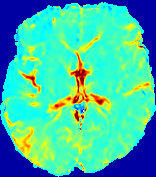

LesionRefer to captionRefer to captionRefer to captionRefer to captionRefer to captionRefer to caption𝐕rgbsubscript𝐕𝑟𝑔𝑏{\bf{V}}_{rgb}Refer to captionRefer to captionRefer to captionRefer to captionRefer to captionRefer to caption𝐕2subscriptnorm𝐕2{\|\bf{V}}\|_{2}Refer to captionRefer to captionRefer to captionRefer to captionRefer to captionRefer to captionRefer to caption3.53.53.52.82.82.82.12.12.11.41.41.40.70.70.70.00.00.0(mm/s)𝑚𝑚𝑠(mm/s)D𝐷DRefer to captionRefer to captionRefer to captionRefer to captionRefer to captionRefer to captionRefer to caption0.0200.0200.0200.0160.0160.0160.0120.0120.0120.0080.0080.0080.0040.0040.0040.0000.0000.000(mm2/s)𝑚superscript𝑚2𝑠(mm^{2}/s)Slice #1Slice #2Slice #3Slice #4Slice #5Slice #6

Figure 4: PIANO feature maps for another patient in the ISLES 2017 training set, where the lesion is located in the right hemisphere. Top row: segmented stroke lesion region (white) on different slices. The corresponding slices for the PIANO feature maps are shown in the following rows.

For a better insight into an estimated velocity field 𝐕𝐕{\bf{V}} and diffusion field 𝐃𝐃{\bf{D}}, we compute the following maps: (1) 𝐕rgbsubscript𝐕𝑟𝑔𝑏{\bf{V}}_{rgb}: Color-coded orientation map of 𝐕=(Vx,Vy,Vz)T𝐕superscriptsuperscript𝑉𝑥superscript𝑉𝑦superscript𝑉𝑧𝑇{\bf{V}}=(V^{x},V^{y},V^{z})^{T}, obtained by normalizing 𝐕𝐕{\bf{V}} to unit length and mapping its 3 components to red, green, blue respectively; (2) 𝐕2subscriptnorm𝐕2\|{\bf{V}}\|_{2}: 222 norm of 𝐕𝐕{\bf{V}}; (3) D𝐷D: scalar field in Eq. 5.

Fig. 3 and Fig. 4 show the PIANO feature maps estimated from two ISLES 2017 patients: all are highly consistent with the lesion in both cases. Details of the blood flow trajectories are revealed in 𝐕rgbsubscript𝐕𝑟𝑔𝑏{\bf{V}}_{rgb} by the ridged patterns and the sharp changes of colors in the unaffected (right) hemisphere, while the flat patterns appearing within the lesion provide little directional information about the velocity and indicate low velocity magnitudes. Velocity magnitudes are more directly visualized via 𝐕2subscriptnorm𝐕2\|{\bf{V}}\|_{2}, from which one can easily locate the lesion where 𝐕2subscriptnorm𝐕2\|{\bf{V}}\|_{2} is low. D𝐷D also indicates lower diffusion values in the lesion, though with less contrast potentially due to the fact that it captures the accumulated effect of CA diffusion at the voxel-level.